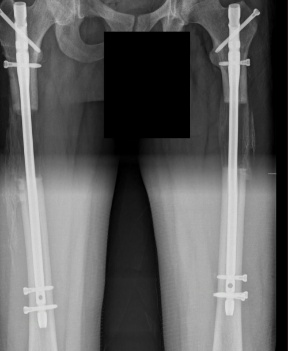

Success Story of Yusuf (8 cm -3.1 inch with lon method)

And I had a psychology like steel for this surgery that was close to my dreams and I believed it There were only minutes left for me to go into surgery and my valuable doctor Prof. Dr. Halil İbrahim Balcı was warning me from the beginning of the process to give up because no one sends you off to this surgery with joy, a real doctor should test the patient’s psychology well. In fact, my doctor’s dissuasive sentences were a test of endurance and faith that a smart person would do, I think my doctor said come and have tea downstairs before the surgery and I passed this test with flying colors when I said let’s do the surgery and then we can have tea :) My process is starting, Limb lengthening istanbul brought me into my house by their car, I am aware that the real test and the difficult road is the process, I could not get out of bed on my own for the first two or three days during the home process after the hospital because I did not have the strength in my body to lift my leg. When limb lengthening istanbul bring me first physical therapy process, I did not have much pain and finally I could lift my leg even slightly, this was very important for me.

The process generally does not go as you planned, especially when there is pain, you can get upset I did not have nerve pain, but my lower legs were aching from time to time at 4.5 cm If we want the pain to decrease, the most important thing is to address them. We can reduce the pain by walking more and moving more. Pin site pain is very severe at 5.6 cm and can suddenly become unbearable and I applied to my doctor and limb lengthening istanbul patient responsible staff during these processes and they intervene in the wound, they widen the bottom of the needle due to tension, intervene in your wounds with a metal and clean the wound. Even the most durable and highest pain threshold patient cannot stop crying and screaming without a doubt. As a result, this The intervention is done for your own good and you feel better after 1-2 days. Especially the pain in the back pin affects your mobility and sleep a lot.